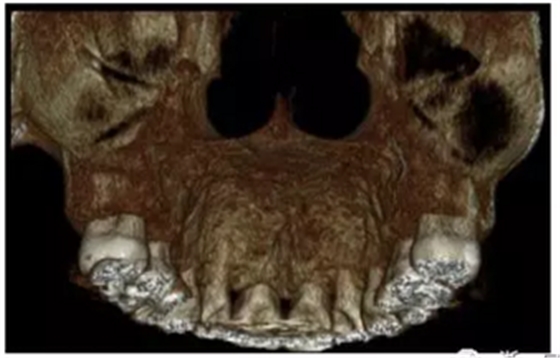

【治療結(jié)果】拆除矯治器后的CT示,上前牙牙槽骨可見骨開裂,另外,在矢狀片層上,可見上前牙的牙根除了根尖1/3區(qū)都沒有腭側(cè)牙槽骨覆蓋。此外,骨開裂在三維重建的影像片上也可見。

完成矯治后9年10個月,再次進行CT 拍攝,對上頜切牙區(qū)牙槽骨進行再次評估,發(fā)現(xiàn)腭側(cè)的上切牙牙根有骨覆蓋。此外腭側(cè)區(qū)域的牙根基本都有較厚的骨皮質(zhì)覆蓋。